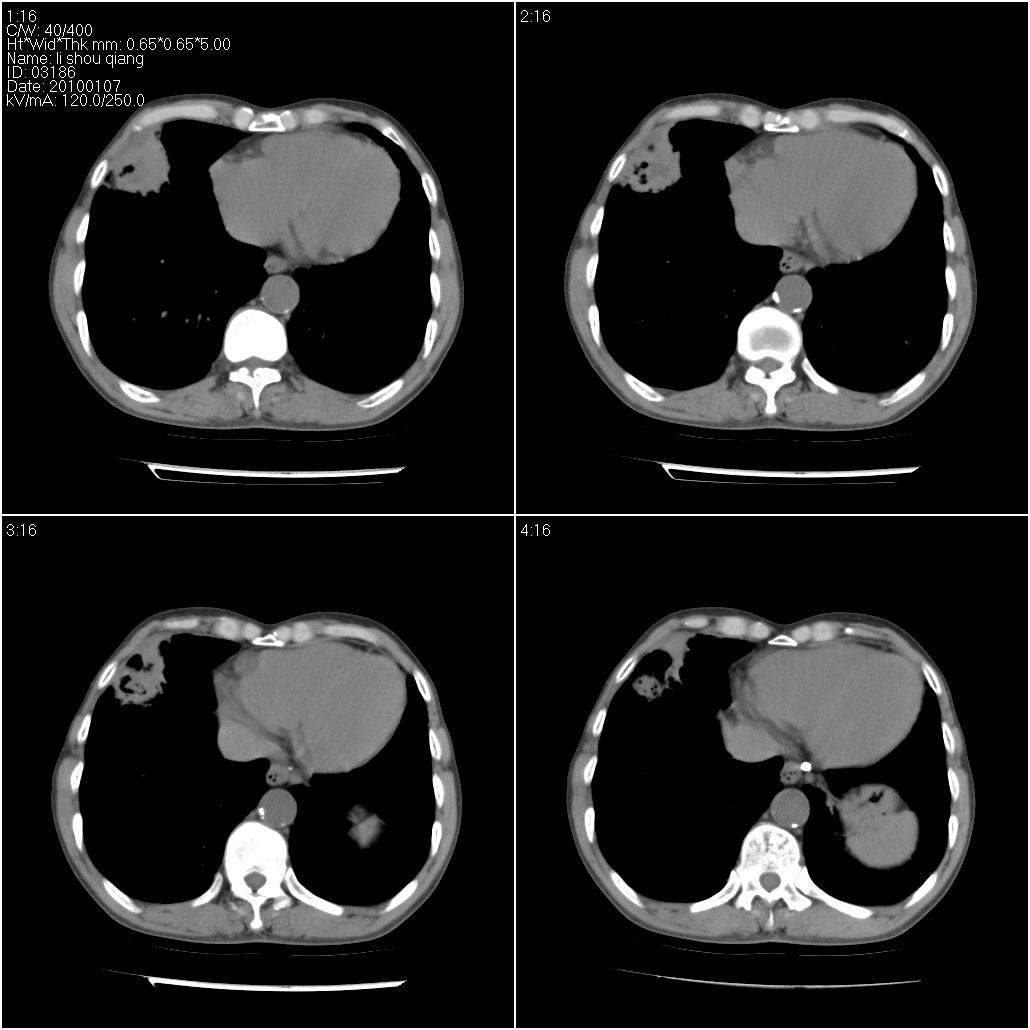

右肺中叶外侧段可见团块影,外形不规则,内见空泡征。左下肺见蜂窝状低密度透亮影,部分层面主动脉旁瘤样突出。考虑右肺中叶外围型肺癌可能性大,左下肺支气管扩张,主动脉弓瘤样突出。

考虑右肺癌可能性大,左下肺支气管扩张,主动脉弓瘤样突出?建议增强

3、建议增强除外主动脉弓息室样动脉瘤。

3、建议冠状位重建除外主动脉弓息室样动脉瘤。